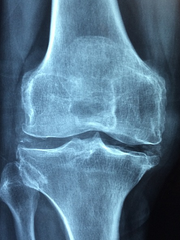

무릎 관절 정보

무릎 관절 증상

관절염은 여러 가지 형태가 있지만, 대개 공통적인 증상이 있습니다. 이러한 증상은 조금씩 나타나거나 급격히 나타날 수 있으며, 다음과 같습니다.

- 관절 통증: 가장 일반적인 관절염 증상으로, 뼈와 연결된 관절 부위에서 통증이 발생합니다.

- 관절 강직성: 통증 때문에 관절을 움직이기가 어려워지며, 아침에 일어나는 시간에 가장 두드러집니다.

- 관절 부종: 관절 주변의 염증으로 인해 부풀어 오르고, 화끈거리거나 뜨겁게 느껴질 수 있습니다.

- 관절 염증: 관절 통증, 부종, 강직성과 함께 관절 주위의 염증이 발생합니다.

- 발열, 피로: 염증과 통증 때문에 발열과 피로가 동반될 수 있습니다.

무릎 관절 원인

무릎 관절 통증의 원인은 매우 다양합니다.

- 골관절염: 무릎 관절의 연골이 마모되어 뼈끼리 직접 마찰됨으로써 발생하는 만성적인 질환이며, 무릎 관절 통증과 강직성을 유발합니다.

- 연골손상: 부상, 나이, 무릎과 같은 관절을 과도하게 사용하는 등의 요인으로 인해 연골이 손상되어 무릎 관절 통증을 유발할 수 있습니다.

- 퇴행성 관절질환: 연령과 함께 무릎 관절을 둘러싸는 무릎뼈와 연골, 인대, 근육 등이 점차 마모되고 약해지며, 무릎 관절 통증을 일으키는 원인이 됩니다.

- 관절염: 관절염은 무릎 관절을 포함한 관절의 염증으로, 무릎 관절 통증, 강직성, 관절 부종 등의 증상이 나타납니다.

- 외상: 스포츠 활동, 교통사고, 낙상 등의 외상으로 무릎 관절에 손상이 생겨 무릎 관절 통증이 발생할 수 있습니다.

무릎 관절 통증의 원인은 다양하며, 적절한 치료를 위해서는 정확한 원인을 파악하는 것이 중요합니다.